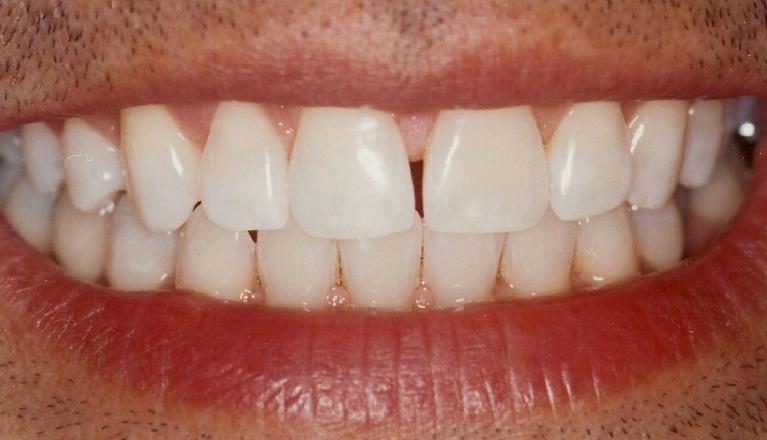

Laminate composite resin veneers

This patient came to our office with severely eroded enamel. This condition can result from excessive use of acidic foods (such as lemons or soda), or other causes.

When the enamel is not present to protect the teeth, the softer dentin underneath is far more vulnerable to further destruction.

This case was restored with composite resin veneers, and was completed in one session. In cases such as this, little or no drilling of the natural tooth structure is necessary.